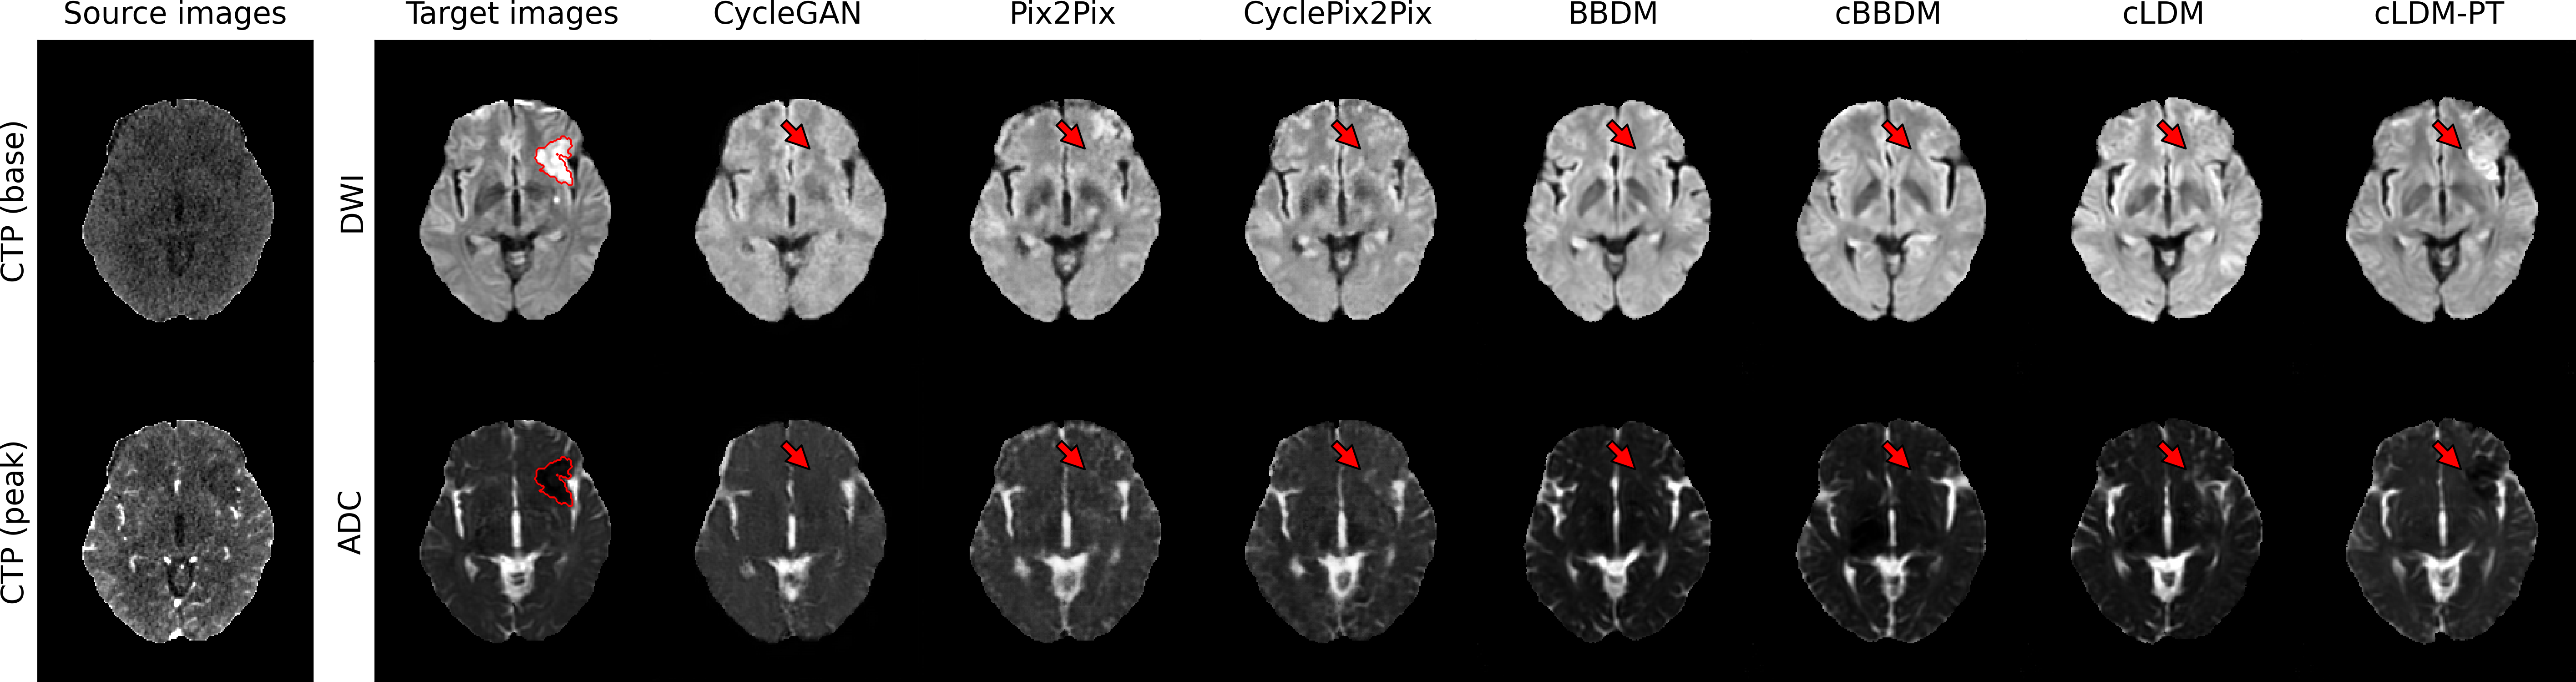

3.2.2 Qualitative Evaluation

Figure 3 visualizes synthesized DWI and ADC from CTP of acute ischemic stroke patients with lesions in various brain regions. Due to low signal-to-noise ratio of CTP, it is difficult to accurately estimate ischemic core volumes. Small infarcts such as lacunar infarcts are also poorly visualized in CTP. These factors make it challenging for generative models to accurately reconstruct ischemic lesions in synthesized MRI. While the diffusion model series generates more realistic images compared to GAN-based models, they encounter difficulty in lesion delineation. Our model, cLDM-PT, excels in lesion delineation and demonstrates exceptional ability to generate accurate and detailed images.